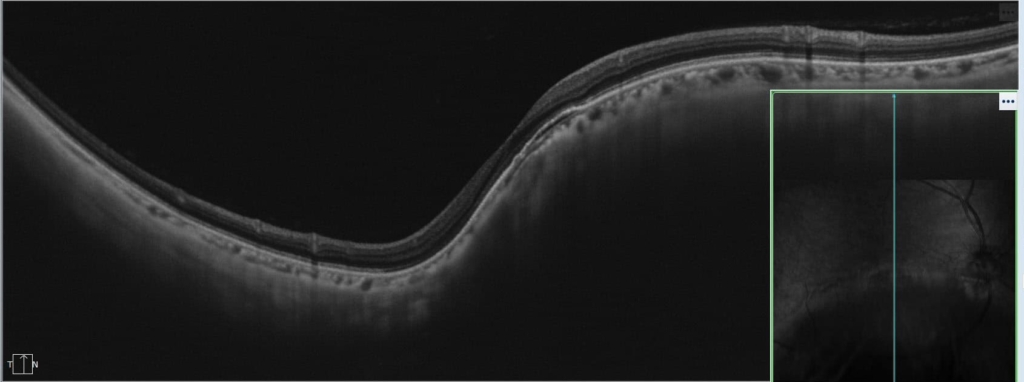

両眼ともに、後部ぶどう腫staphylomaの上縁に一致して乳頭下縁から黄斑を横断するように帯状の網脈絡膜の萎縮巣がみられる。また後部ぶどう腫領域に一致して網膜・脈絡膜が菲薄化しているため、紋理眼底tessel lated fundusがみられる。

後部ぶどう腫の上縁に漿液性網膜剥離(SRD)がみられる。この後部ぶどう腫と正常部の境界付近に脈絡膜新生血管の発生を見ることもあるため、注意が必要。